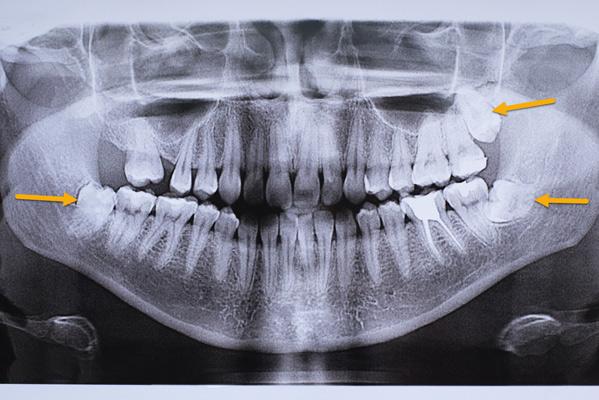

Операция начинается с тщательной диагностики: КТ для оценки объёма кости, моделирование положения зуба, подготовка ложа. Затем удаляют донорский зуб с минимальной травмой периодонта и сразу переносят в подготовленное место, фиксируя шиной на 1-2 недели. Важно: в первые месяцы зуб требует щадящей нагрузки и регулярного контроля приживления.

4. Рентген-контроль — снимки через 3, 6 и 12 месяцев показывают динамику приживления.